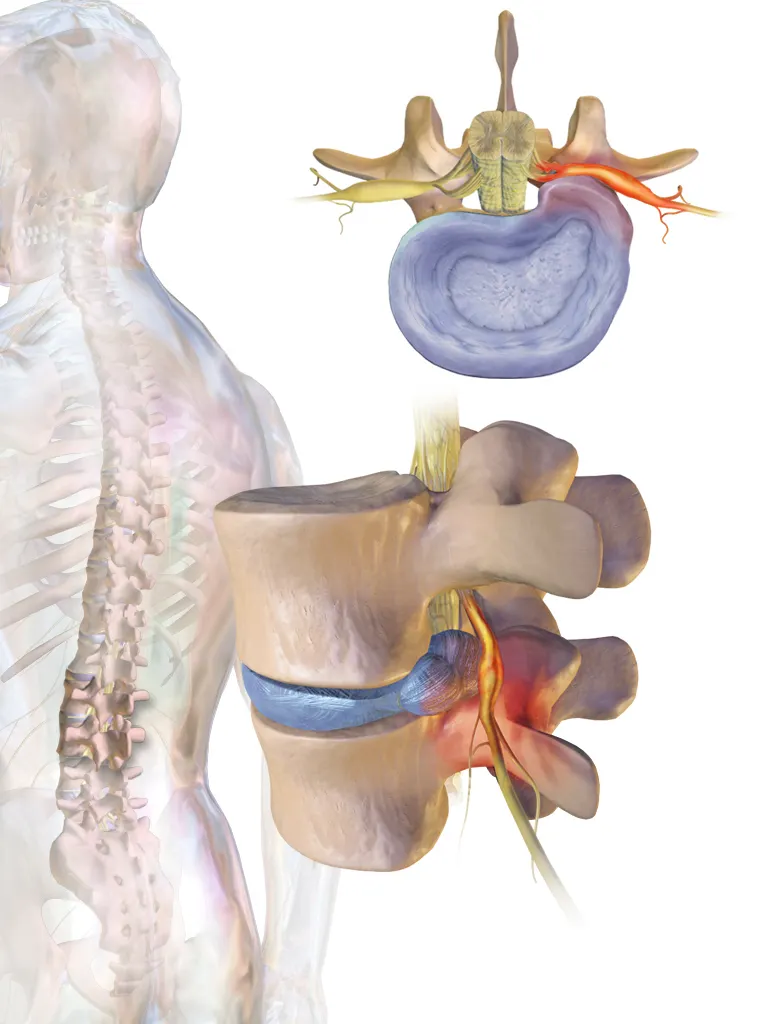

Spondylosis, or degenerative changes of the spine, develops gradually over many years as a result of the natural aging process and biomechanical loading of the spine. It is widely believed that the entire process of spondylosis begins with intervertebral disc degeneration and then progresses through several overlapping stages. This sequence of events is known as the degenerative cascade.

Over time, the intervertebral discs lose their elasticity, small fissures develop, nutrient diffusion decreases, and the discs gradually dehydrate and lose height. As disc degeneration progresses, disc herniation (disc protrusion) may occur.

Loss of normal disc function leads to increased compressive forces on the vertebral bodies, which promotes the formation of bony outgrowths (osteophytes). In addition, disc degeneration results in reduced segmental stability, increasing mechanical stress on the facet joints. As a consequence, degenerative changes of the facet joints (facet joint osteoarthritis) also develop.

Radiculopathy occurs when the nerve roots emerging from the cervical or lumbar spine are compressed or irritated. It is less common than neck or lower back pain.

In younger patients, typically in their 30s and 40s, the most frequent cause is a herniated disc, which presses on the nerve. As people age, degenerative changes become the main cause: disc degeneration is the leading cause in the 50s and 60s, while in the 70s, osteophytes or spondylophytes narrowing the nerve exits are usually responsible.

In the lumbar spine, nerve compression is commonly referred to as sciatica. The main symptom is lower back pain radiating down the leg, often reaching the foot.

Herniated intervertebral discs, thickened spinal ligaments, hypertrophic facet joints, and osteophytes can narrow the spinal canal and compress the cervical spinal cord. This condition is called cervical myelopathy.

4. Lumbar spinal canal stenosis and neurogenic claudication

Lumbar spinal canal stenosis occurs when the spinal canal narrows, compressing the nerve roots on their way to the legs. This narrowing can result from degenerative changes, including osteophytes, ligament thickening, or herniated discs.

MRI is the most reliable method for visualizing nerve structures and soft tissues. It provides a detailed view of nerve or spinal cord compression and can detect pathological changes such as disc herniations, osteophytes, or ligament hypertrophy. However, because degenerative changes are often present in asymptomatic individuals, MRI is typically reserved for clinically indicated cases.